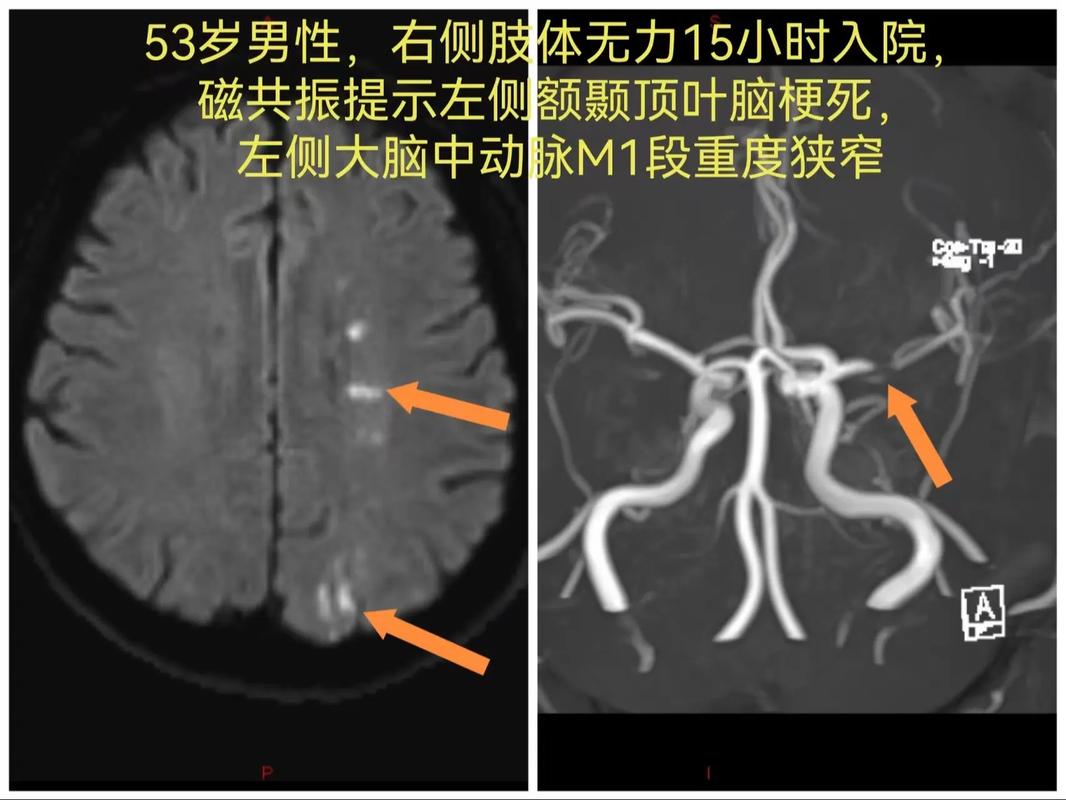

- CTA(CT血管造影)或MRA(磁共振血管造影):能更清晰地显示颅内血管的情况,评估狭窄范围和程度,医生会根据情况建议复查间隔。

- DSA(数字减影血管造影):是诊断血管狭窄的“金标准”,但有创性,通常不作为常规复查手段,多在考虑介入治疗时使用。